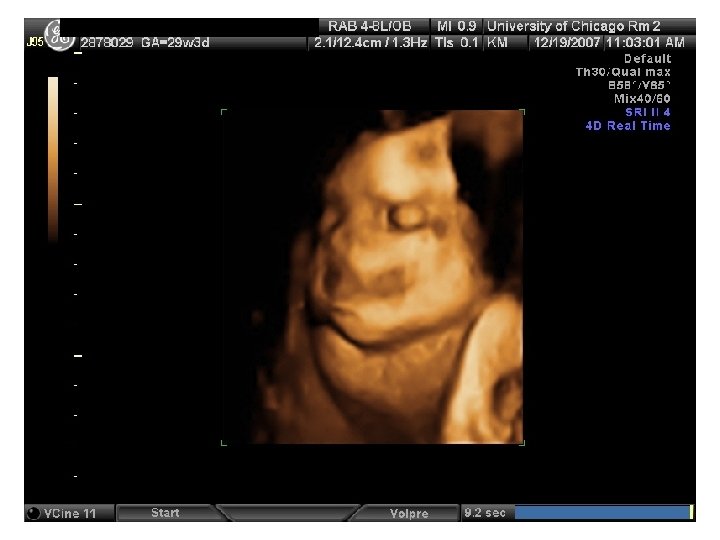

QUIZ What is Your Diagnosis? Case: Patient J. F. 30 years old, at 32 week gestation. Presented with the following pictures.

Answer: a) Trisomy 21 b) Non-immune Hydops c) Paravo virus Infection